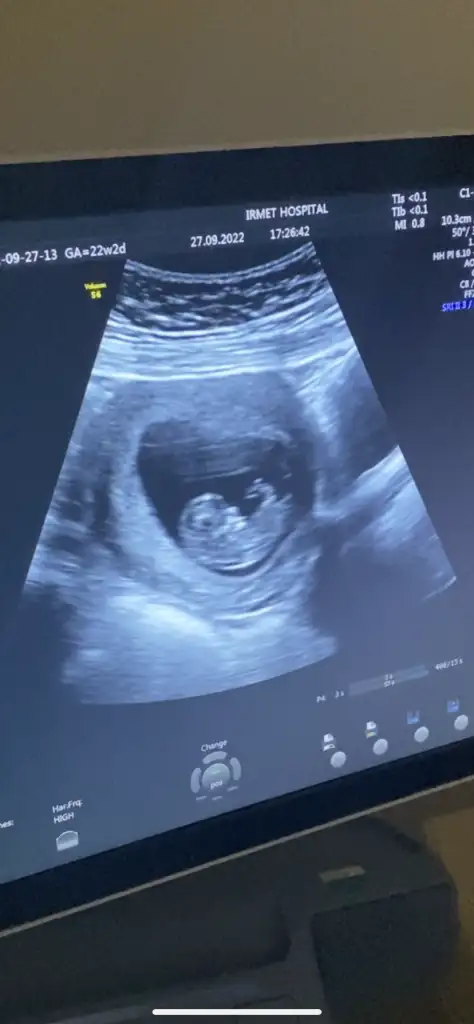

Canım ultrasonda niye 22 hafta 2 günlük yazıyor yanlış mı yazılmışBebişe nub a göre yorum yapabilecek var mı kızlarr aşırı merak ediyorum B BarbieveKen göreveebirde kalp atışı dk da 144 dedi araştırmalarıma göre 140 ın üstü kız yazıyor

ay öyle güzel oynuyordu ki pıtır pıtırdı eller ayakları